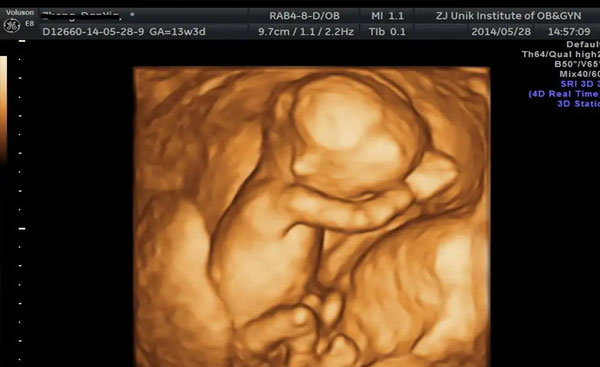

想要在B超图中想要找出奥密,最在是在怀孕15周之后做四维检查,这个是时候的胎儿发育到了一定的程度,可以通过生殖器来进行初步的分辩,如果在B超图中看到有凸出的东西、圆圆的蛋蛋就是男性的生殖器管,因此是男孩。如果在B超图中只看到三条白线或是没有明显看到三条白线,就要看看胎儿的两腿之间有没有突出的东东,如果中间有小凹槽的就是女宝宝。

如果有仔细的看彩超单,就会发现彩超单上顶关最右边有两行字母,是由英文字母加数字组合的,日期是在第一行,时间是在第二行。在第一行是M开头,那就是male男,是F开头就是female女,T指的是时间。还有一处很小的英文字母Qual high,在Qual high处是1就是女孩,2就是男孩。